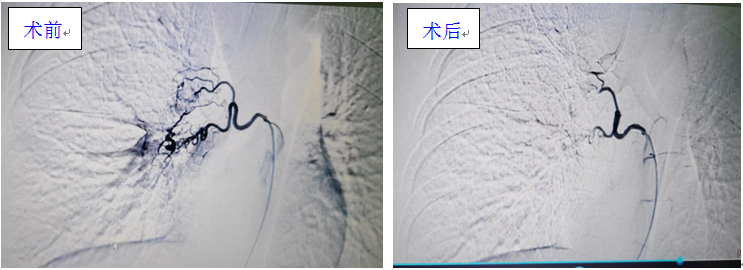

对此,科室与放射科介入专业孙向阳主治医师联合讨论,患儿出血量较多,支气管动脉压力较高,责任血管可能性大,很可能是支气管动静脉畸形。为此,儿科呼吸专业主任李福海与孙向阳等医师联合,于3月23日行支气管动脉造影术,可见右侧支气管动脉明显迂曲扩张,并可见肺动脉显影,证实为支气管动脉-肺动脉瘘,并行右侧支气管动脉栓塞术,给予栓塞后未再见支气管动脉远段及肺动脉显影。